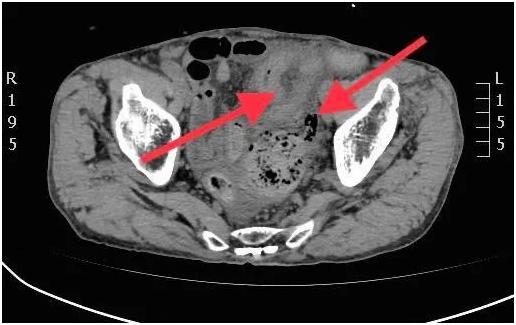

CT影像肠壁增厚水肿

CT提示患者乙状结肠肠壁增厚,局部明显水肿,周围可见气泡影,结肠占位,傅传刚教授高度怀疑结肠憩室,穿孔可能。急诊开腹探查,见腹腔内淡黄色渗液约300ml,腹腔内广泛粘连,全小肠及结肠扩张明显,乙状结肠憩室约3cm,破裂坏死,盆腔积血和粪便样液体约200ml,周围包裹黏连。升结肠憩室约1.0cm,十二指肠与空肠交界处憩室约2.0cm。术中诊断:急性弥漫性腹膜炎 乙状结肠巨大憩室坏死穿孔 升结肠憩室 小肠憩室 。傅传刚教授与周主青教授团队共同为患者实施乙状结肠切除术+结肠造口术+升结肠憩室切除术+小肠憩室切除术+腹腔粘连松解术。吸出盆腔积血及积液,解除粘连。随后游离并切除升结肠、小肠憩室,切除部分结肠及直肠,结肠残端吻合于皮肤造口。手术用时5小时,患者安全返回病房。